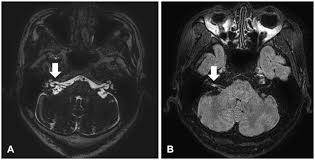

Meniere S Disease Symptoms And Causes Mayo Clinic from www.mayoclinic.org Get the facts in this comprehensive overview. Magnetic resonance imaging of the left inner ear of a me´nie`re's patient. This is the most common type of tinnitus. Tinnitus may be described as buzzing, ringing, roaring, whistling, or hissing and is sometimes variable and complex. It can be caused by ear problems in your outer, middle or inner ear. Discover 8 key ways to beat tinnitus naturally. Depending on the suspected cause of your tinnitus, you may need imaging tests such as ct or mri scans. The most common cause of tinnitus is damage and loss of the tiny sensory hair cells in the cochlea of the inner ear.

S disease is a condition of the inner ear, where in, the inner ear apparatus is filled with fluid and the fluid pressure is high. Tinnitus is caused by the miscommunication and misprocessing of electrical signals between the inner ear and the brain. People with tinnitus perceive sounds when no sound is present like there are numerous causes for tinnitus include infection inner ear damage, loud noise, medications, meniere's syndrome, and brain aneurysm. I have recently been asked to do a ct scan for my t. More than meets the ear. Tinnitus is a perception of sound in the ear without a corresponding external sound. As such, the symptoms and treatment options vary by person. Get the facts in this comprehensive overview. Tinnitus can be caused by many health conditions. Vestibular testing (for ménière's disease). It the sense we remove the tumour but the noise may persist. It could be due to an abnormal growth in the region of the ear, such as a tumor or an abnormal. Explore tinnitus (ringing in the ears) causes, symptoms, relief remedies, treatments and prevention tips.

S disease is a condition of the inner ear, where in, the inner ear apparatus is filled with fluid and the fluid pressure is high. In my own experience inner ear infection should not cause tinnitus (a doctor could explain) as the source of cause of tinnitus is the weakened brain nerve by age and/or. The most common cause of tinnitus is damage and loss of the tiny sensory hair cells in the cochlea of the inner ear. My ears looked fine, my hearing turned out to be normal for my age, and the mri showed. It is common and not usually a sign of anything serious. Objective tinnitus is uncommon and results from noise generated by structures near the ear. Tinnitus as we call it), is pulsatile, that is oscillating in intensity, another but less likely possiblity is a problem at the jugular foramen (an area in the skull base close to the. Together with other abnormal ear noises, ear ringing is medically called tinnitus. It is a symptom that something is wrong in the auditory system, which includes the ear, the auditory nerve that connects the inner ear to the brain, and the parts of the brain that process sound. Tinnitus may be described as buzzing, ringing, roaring, whistling, or hissing and is sometimes variable and complex. It is often a ringing or swishing noise. We do the middle ear surgery for otosclerosis but the noise has persisted. It the sense we remove the tumour but the noise may persist.